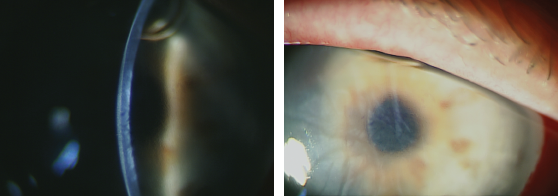

On April 18, 2017, the patient underwent central DR with a diameter of 5.0 mm, and the condition of the cornea in the right eye after 2 days is shown in Figure 3. The uncorrected visual acuity of the right eye was 0.3, and the IOP was 10 mmHg (as measured using the Icare tonometer). Excessive edema and folds in the deep stroma were observed as well as multiple epithelial bullae in the optical zone and transparent corneal periphery with a well-defined endothelial pattern. The margin of DR could not be visualized, although the deeper parts remained unchanged. The patient was examined every week (Figure 4), and after 2 weeks post DR, she underwent accelerated CCL (intensity: 9 W/cm2, 10 min exposure). Two weeks after CCL, the uncorrected visual acuity was 0.3, and the CCT was 546 µm. Stromal edema and the number of bullae were reduced, and the margin of DR was visualized (Fi gures 5 and 6). One month after CCL, the uncorrected visual acuity increased to 0.5 (Figure 7 shows the cornea), and a confocal microscopic examination revealed single ECs in the area of DR (Figure 8). The complete restoration of corneal transparency occurred 4.5 months after surgery, with the uncorrected visual acuity reaching 1.0, CCT of 553 µm, and ECD of 1546 cells/mm2 (Figures 9–11).

Fig. 8. Confocal microscopy of endothelial cells (single endothelial cells are visible)

Fig. 9. Confocal microscopy of endothelial cells 1546 cells/mm2 (а); morphological characteristics of endothelial cells by confocal microscopy (b)

Fig. 10. Cornea of the right eye (arrows indicate the border of the descemetorhexis)